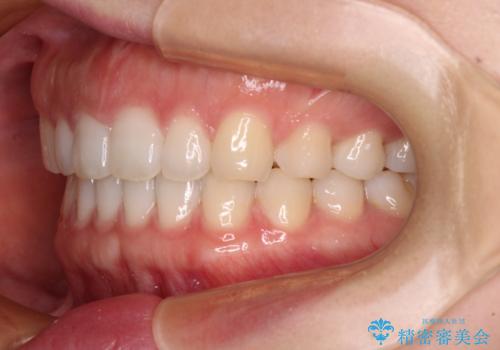

すきっ歯とオープンバイト インビザライン・ライトで改善

オープンバイトのため、奥歯に負担のかかる咬合状態であったので、矯正治療を提案したところ、希望をされました。

すきっ歯程度の軽度の歯列不正であったため、インビザライン・ライトにより咬合改善を行うこととしました。